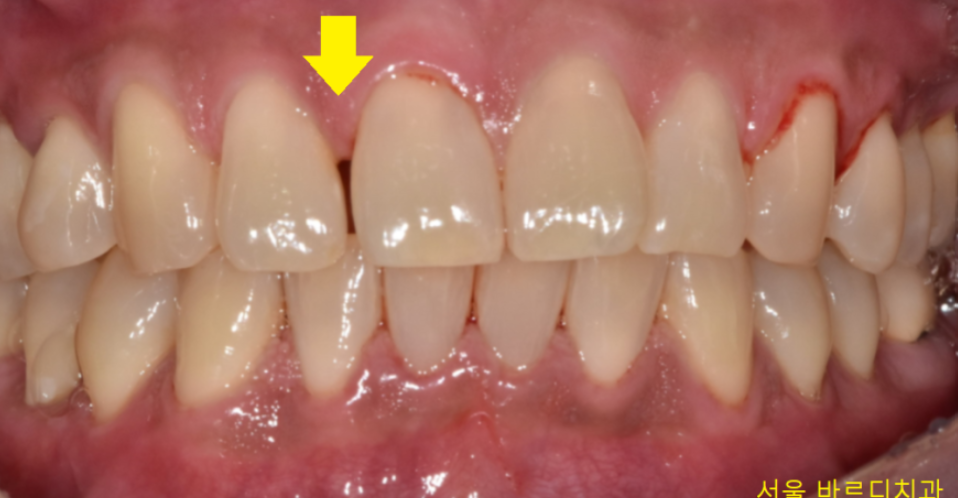

벌어진 앞니 레진으로 공간을 없애드렸습니다.

사진만 봐서는 어떤게 레진이고

내 치아 부위가 어디인지

구분이 잘 안가시겠죠~??

레진이라는 재료가

치아 색깔과 똑같아서 구분이 잘 안가실꺼에요~

그만큼 심미성이 요구되는 앞니에는

딱! 알맞은 치료입니다.

어디가 변했는지 바로 보이시겠죠~?

앞니 레진은 고도의 집중력이 필요합니다.

심미적이기도 하고

모양을 옆에 치아와 비슷하게 만들어서

티가 나지 않도록 떼워드리는게 중요하거든요~